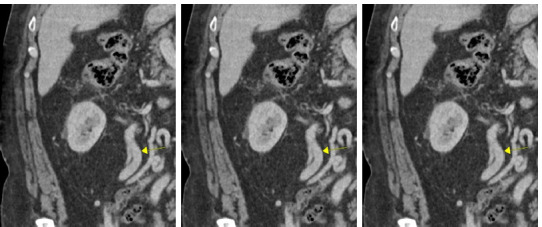

This article is a case report of a 62-year-old male with a left-sided renal cell carcinoma (RCC) with a level II inferior vena cava (IVC) thrombus and caval occlusion. He was managed with open left radical nephrectomy and juxtarenal cavectomy. To preserve right renal venous drainage, the right renal vein was anastomosed to the right gonadal vein. He has not had any renal functional decline or disease recurrence with 3 years of follow-up. The focus of this article is to discuss this distinctive method for vascular reconstruction as an option for right renal venous drainage following left nephrectomy and juxtarenal cavectomy.